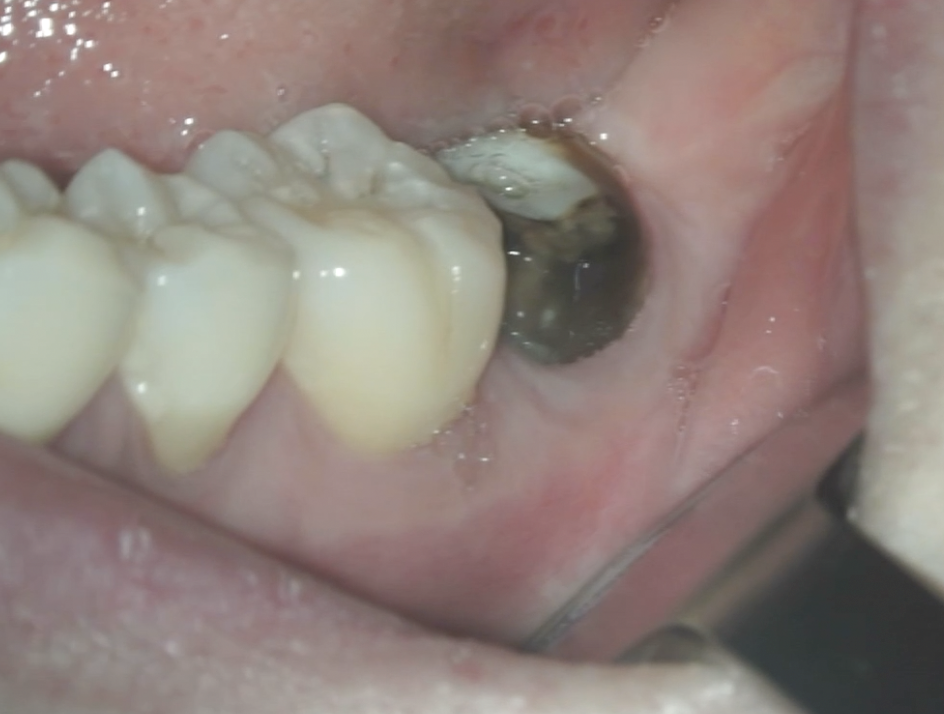

初診時にあった歯肉の腫脹(↓)は消失していた。